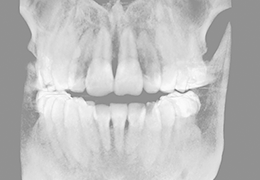

ANYTHINK 经导管主动脉瓣膜置换术分析系统